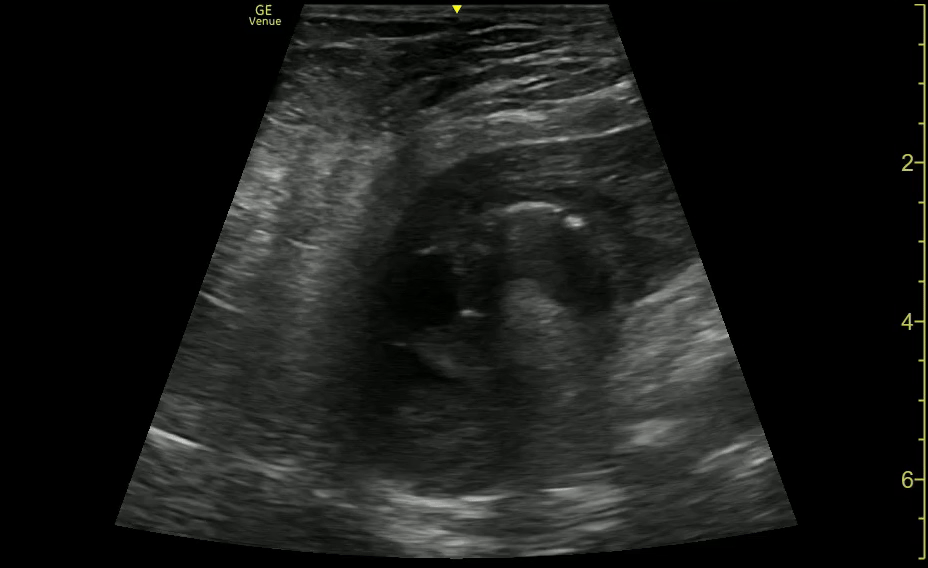

Intussusception